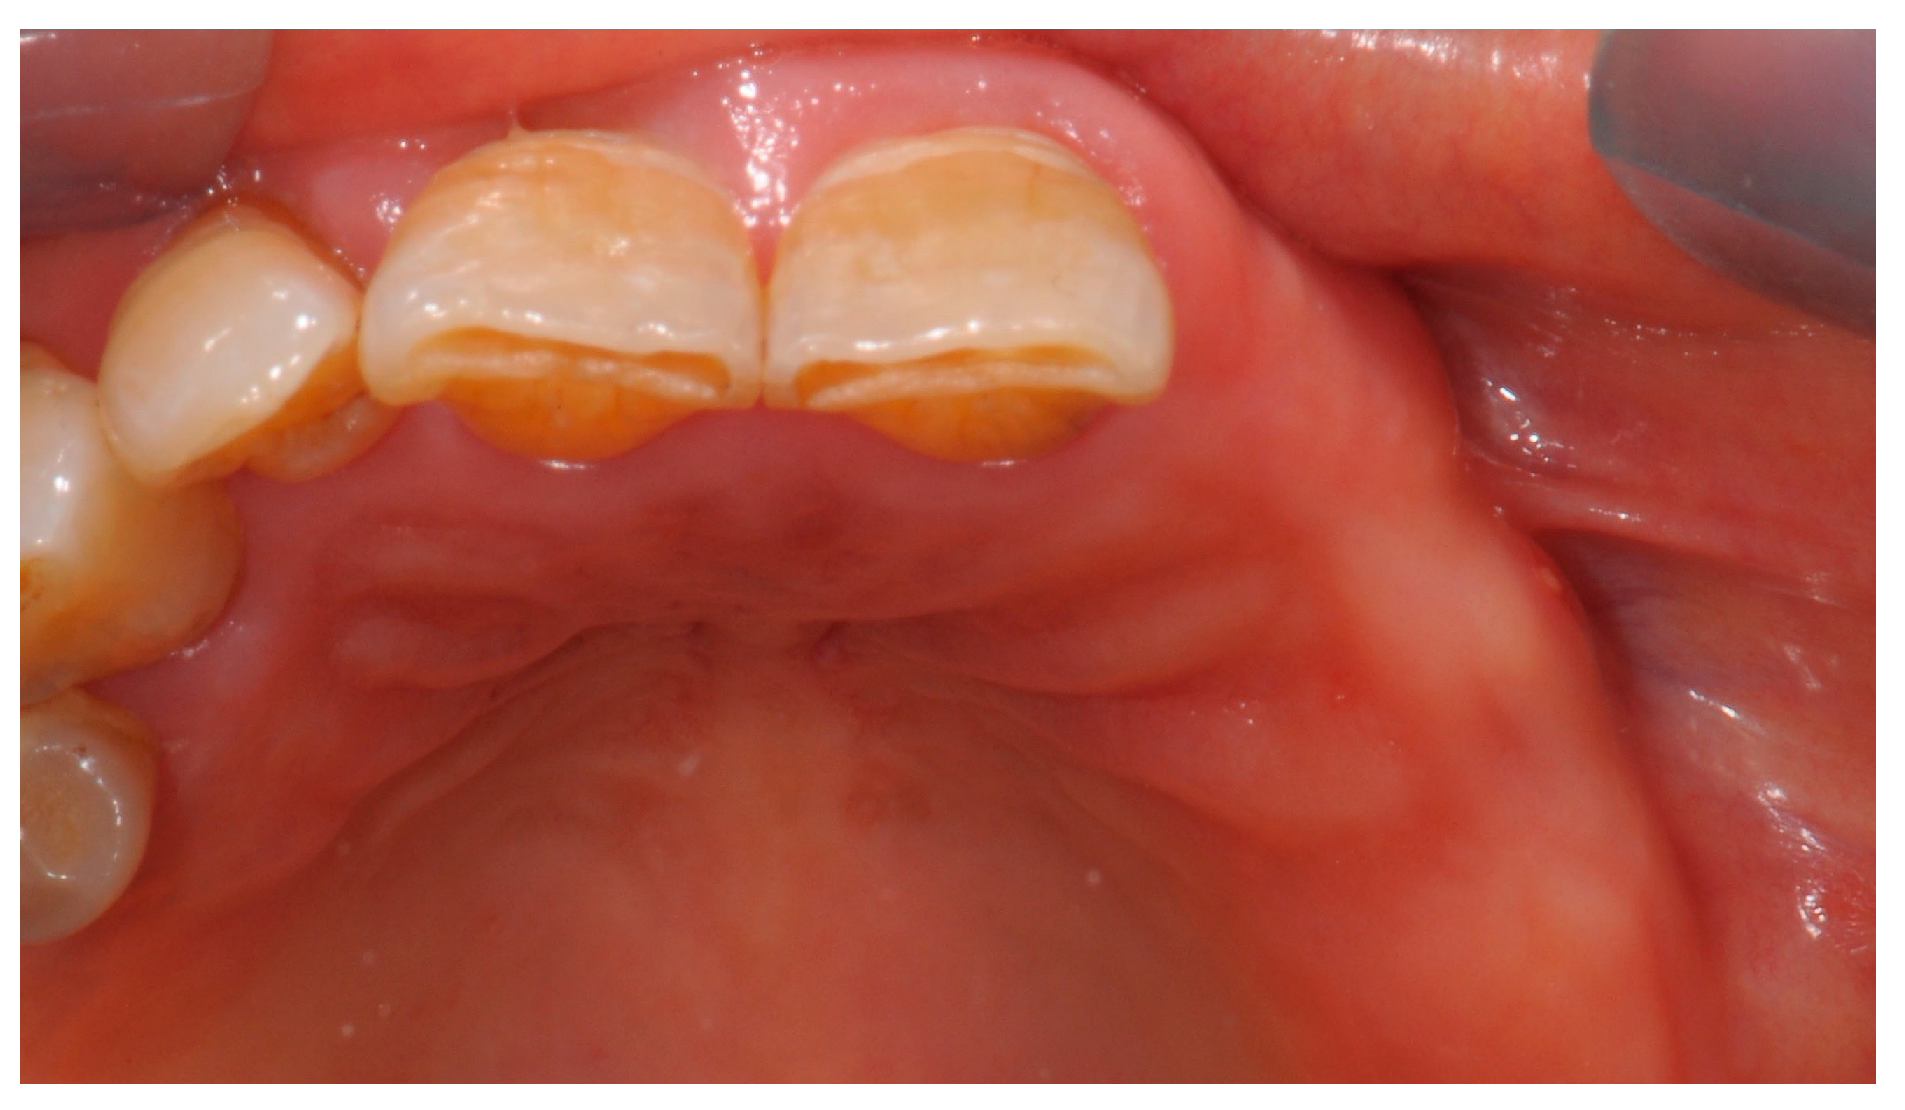

2. Case Report